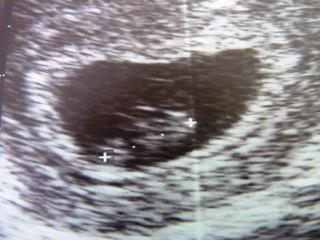

ja som bola včera u doktora,podla poslednej MS je to 7 tt,podla ultrazvuku 6tt,mám ísť o 3 týždne tak uvidíme,zle mi našťastie nie je,len v jedno ráno som zvracala 2x,ináč vpohode,

@zuzanka.j Super fotka, vynikajúce že je všetko v poriadku. Ja tehu knižku dostanem až na konci marca ☹ alebo začiatkom apríla ☹ moja lekárka ju skôr nedáva. 😒